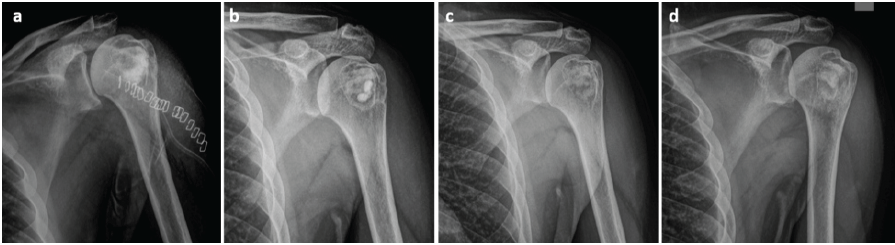

Contrast was injected to delineate the boundaries of the lesion, and the mass was excised in toto. Gross examination revealed a soft yellow mass with multiple septations enclosed within a thin capsule. Complete excision was confirmed using fluoroscopy. Extended curettage was performed using hydrogen peroxide. The resultant cavity was filled using bioabsorbable antibiotic-impregnated polymethylmethacrylate beads along with autologous bone graft harvested from the ipsilateral iliac crest (Fig. 3).

Figure 3: (a) Immediate post-operative radiograph following excision, curettage, and packing of the cavity with bone graft and antibiotic-loaded cement beads, (b) 3-month and (c) 5-month post-operative radiographs demonstrating progressive graft incorporation, and (d) 8-month post-operative radiograph showing complete graft incorporation and cavity consolidation.

Histopathologic analysis revealed the tissue to have fragments of fibroadipose tissue and fibrocollagenous cyst wall devoid of any lining. A focal collection of lymphocytes and pigment-laden macrophages was noted. Postoperatively, the patient reported a significant reduction in pain and was able to resume his activities of daily living by 2 weeks. Functional assessment using the disabilities of the arm, shoulder, and hand questionnaire [11], which evaluates upper extremity function through 30 items scored from 1 (no difficulty) to 5 (severe difficulty), demonstrated improvement from a score of 35 at 2 weeks postoperatively to 5 at 4 weeks, indicating substantial enhancement in functional capacity and quality of life.